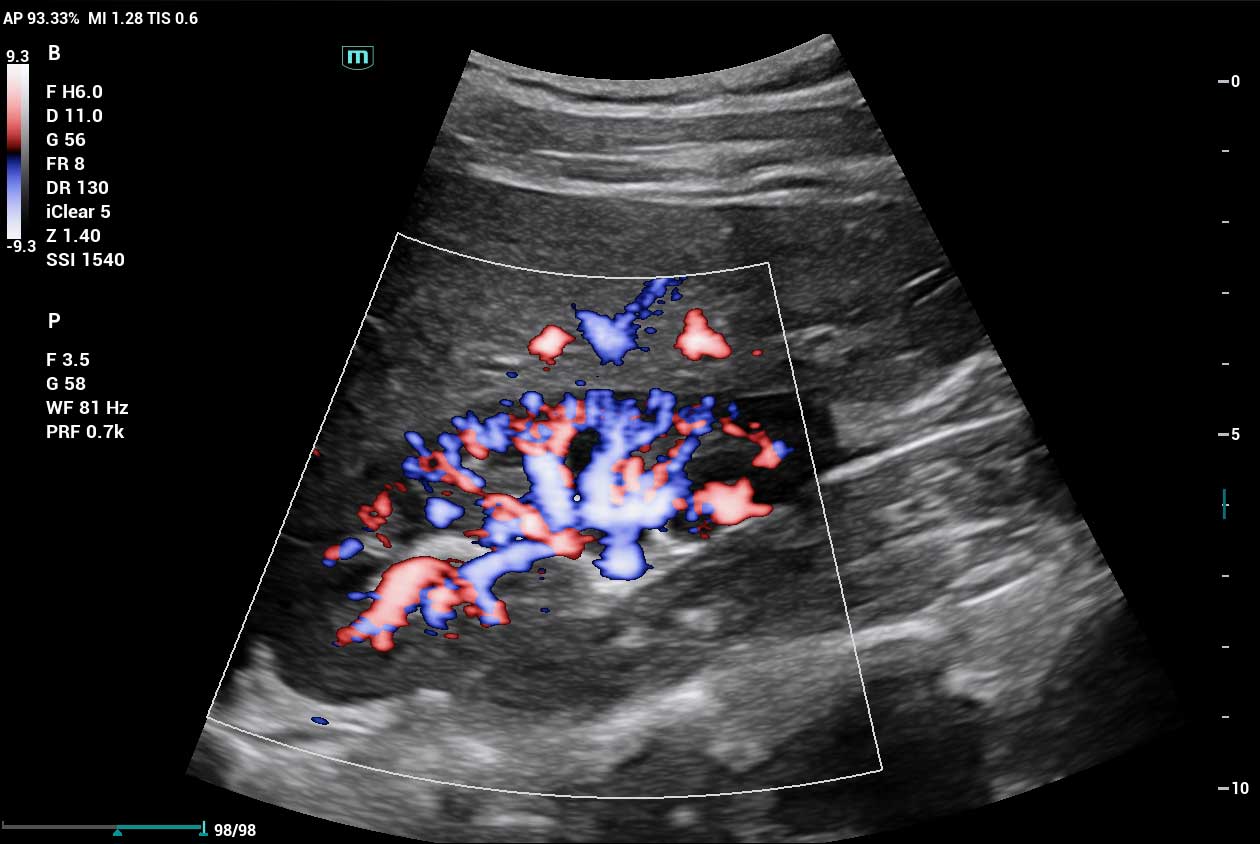

Clinical Images